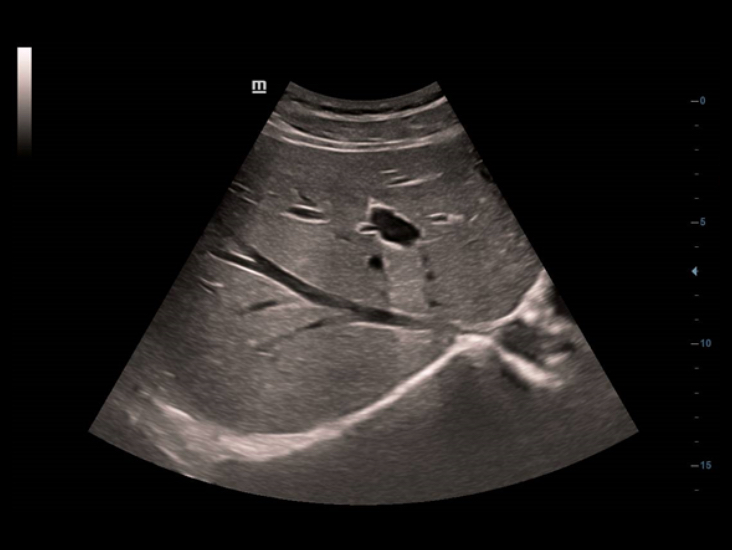

?ok y?nlÞ d?nÞ?tÞrÞcÞ kombinasyonuyla, Full HD ?zellikli DC-40, geni? bir uygulama yelpazesinde en iyi performans? sunar ve ?ok ?e?itli hasta tiplerinde geli?mi? g?rÞntÞ kalitesi sunar.

?rolojik ??zÞm

Lineer/d??bÞkey ve ?ift mikro-d??bÞkey dahil, ?zel olarak tasarlanm?? ?ift kanatl? d?nÞ?tÞrÞcÞler, zihninizi daha az yoracak ?ok y?nlÞ Þrolojik ??zÞmÞ destekler.